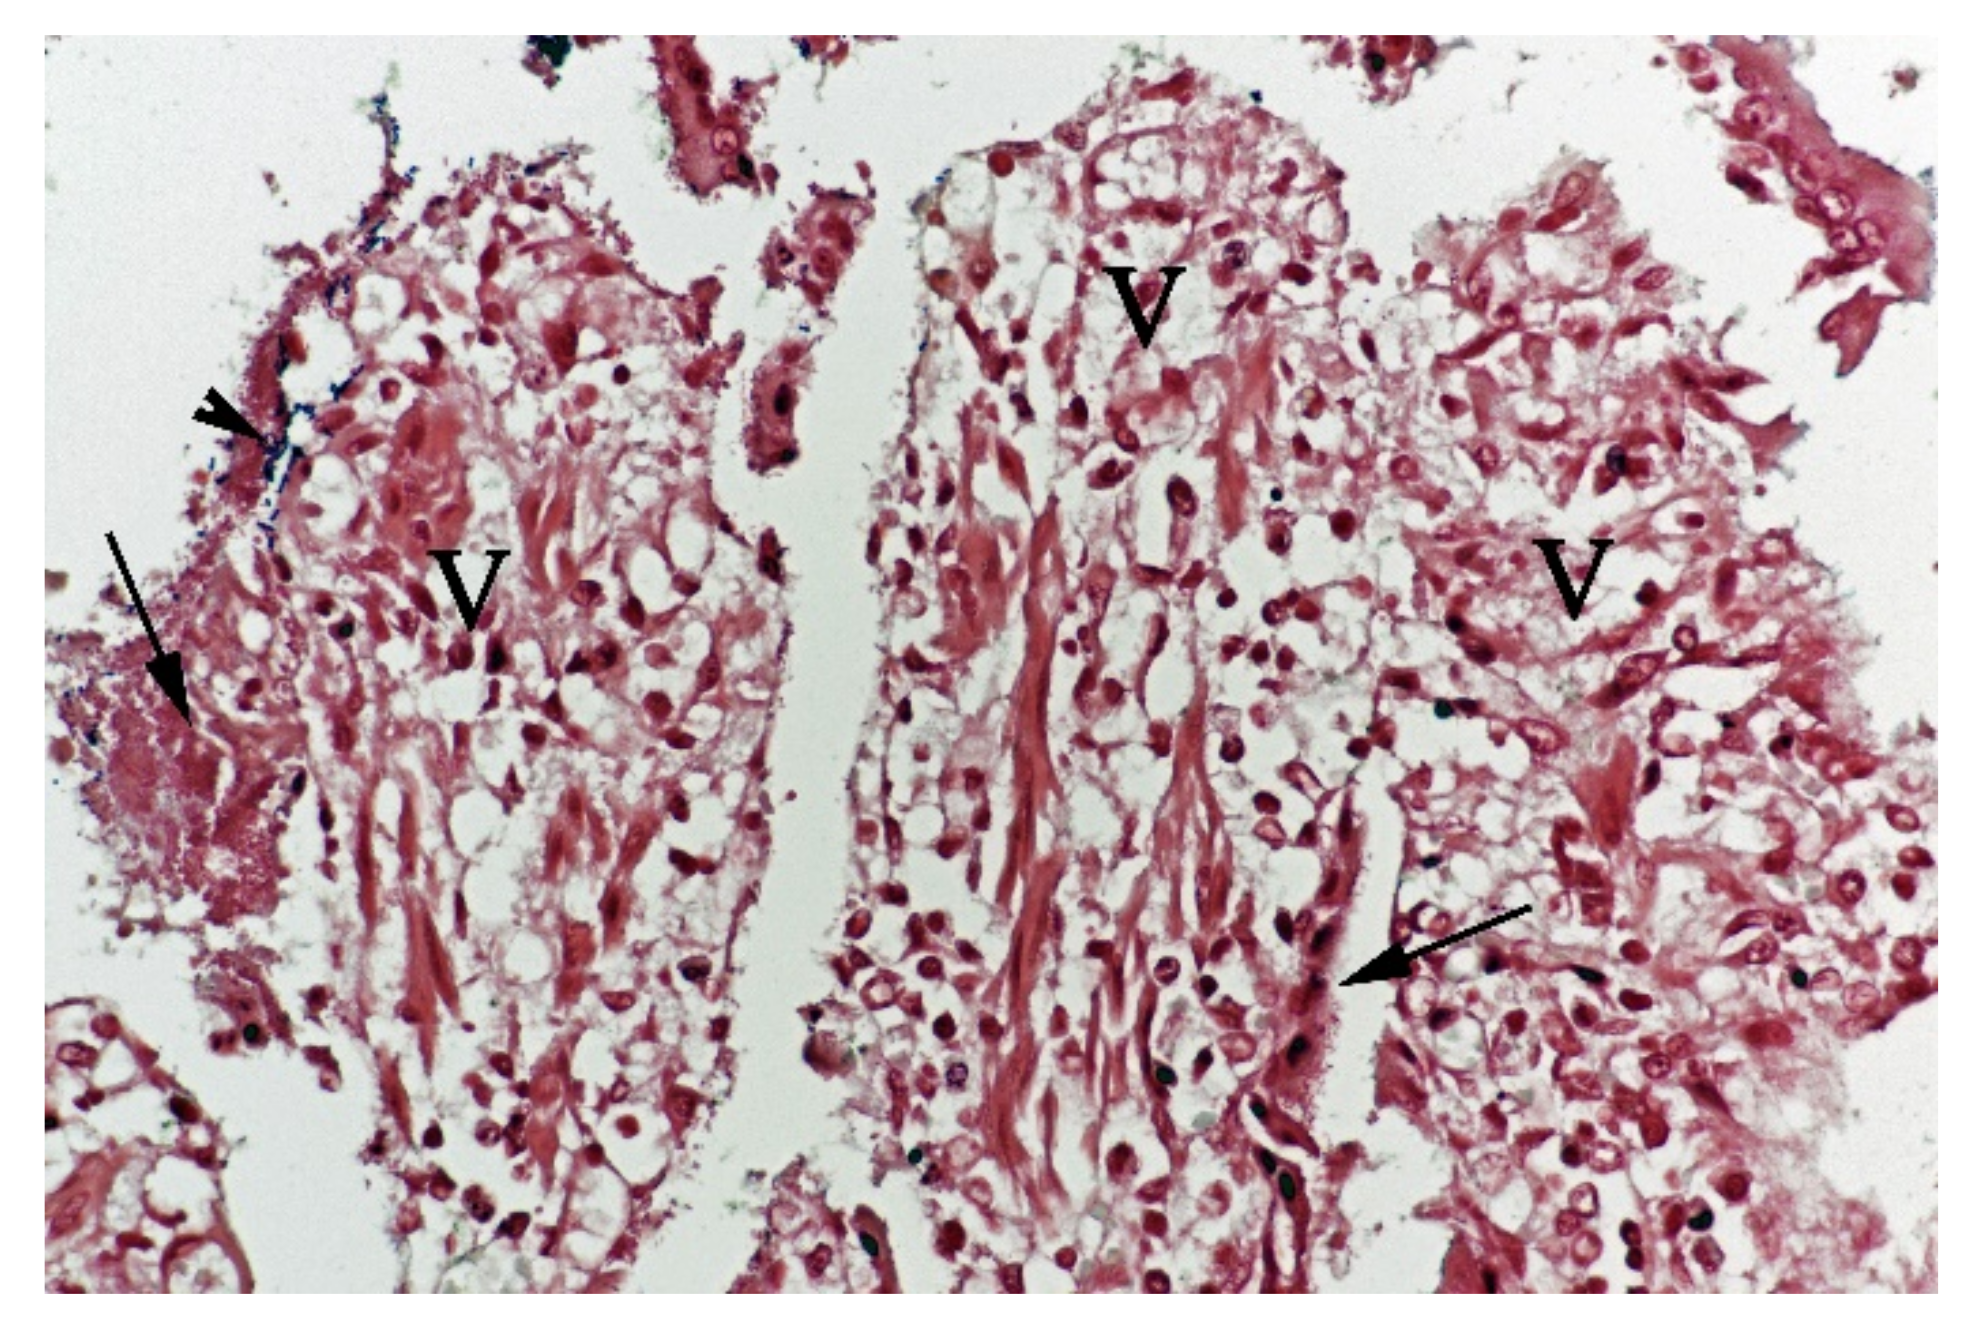

Figure 5.

Histological section from small intestine dog with acute haemorrhagic diarrhoea, Gram-stain. Large amounts of small Gram-negative rods (arrows) were located as single bacteria or thick layers close to the surface of the villi (V). Small amounts of large Gram-positive rods (arrowhead) were present in the clusters of Gram-negative bacteria.

In contrast, the small intestinal mucosa showed dramatic changes with diffuse loss of surface epithelium and loss of architecture with collapse of the villi lamina propria. In some of the dogs, necrosis of intestinal epithelial cells was observed, and multifocal haemorrhages were seen in the deep lamina propria and submucosa (Figure 4). Gram-stained sections showed rich amounts of small Gram-negative rods, located as single bacteria or thick layers close to the surface or as larger clusters deeper in the collapsed lamina propria (Figure 5). Additionally, varying, but often rich amounts of large Gram-positive rods often adherent to the denuded or naked remnants of the villi lamina propria, were observed. The histopathological changes in the large intestine were similar to the findings in the small intestine, with the observation of the same types of bacteria on the surface and in the lamina propria.